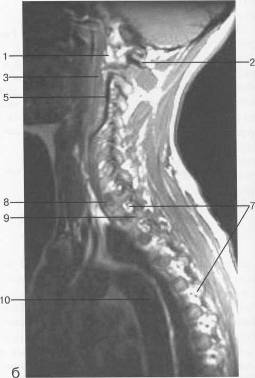

Гиполордоз шейного отдела: диагностика и лечение